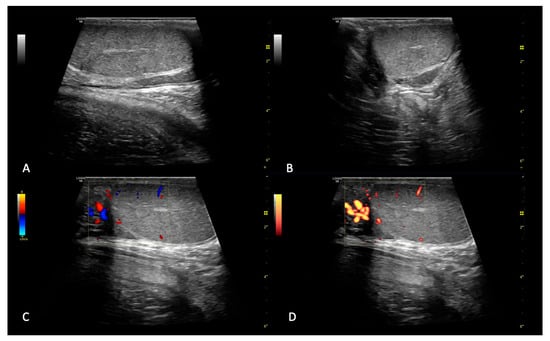

2.1.1. B-Mode and Doppler Examination

2.1.2. SE and 2D SWE Examination